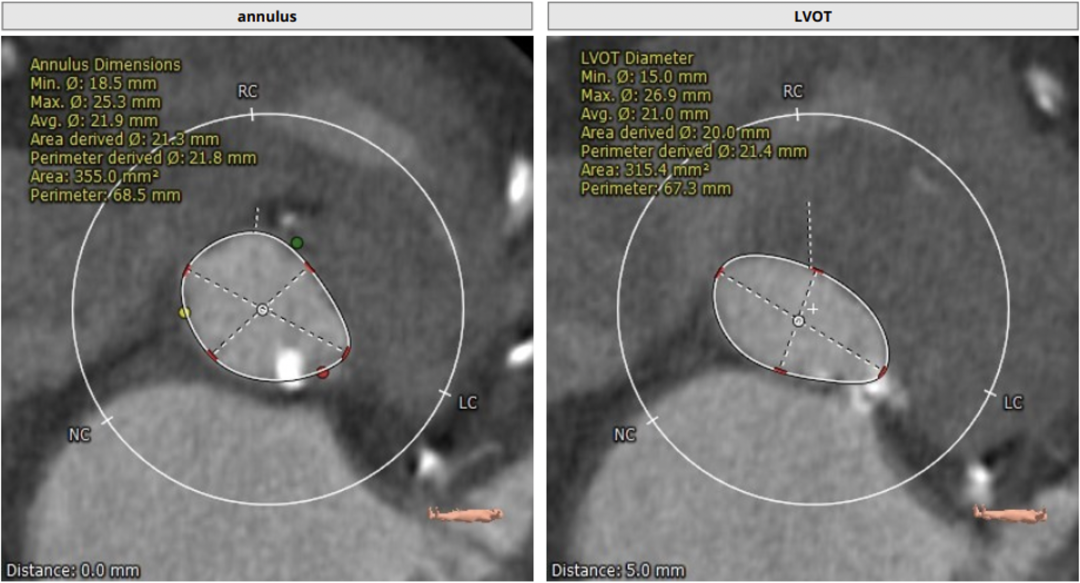

瓣环平均直径:21.8 mm,左室流出道平均直径:21.4 mm

左室小,心肌肥厚

CT评估显示主动脉瓣为三叶瓣,钙化积分:121.5 mm³,轻度钙化。左冠高度:15.3 mm,右冠高度:16.5 mm,冠脉高度可,法式窦结构大,左室小,心肌肥厚,升主动脉未见明显扩张。结合患者主动脉根部情况及病情等综合因素,决定使用VenusA-Plus®可回收输送系统,经由右侧股动脉入路拟植入L23型号瓣膜完成此次手术。